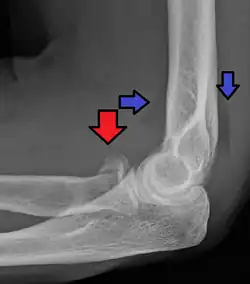

| Radial head fracture (red arrow) with posterior and anterior sail sign (blue arrows) | |

Radial head fractures are diagnosed from a clinical assessment and diagnostic imaging.[7] Symptoms may include pain or tenderness at the radial head, bruising, swelling, and a limited range of motion of the injured elbow.[2] Diagnostic imaging may include ultrasound, plain radiography (x-ray imaging), Computed tomography scan (CT), and magnetic resonance imaging (MRI).[2][4] A fat pad sign may be present on diagnostic imaging and may indicate a radial head fracture.[5]